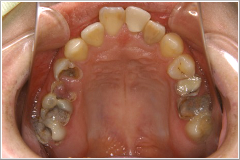

正月気分間覚めやらぬ1月8日、「前歯が折れてしまって、成人式に出られないんです。何とかならないでしょうか?」 という電話がありました。晴れの舞台に“歯っ欠け”ではさすがに気の毒で、「仮歯くらいなら、なんとかなりますよ」と答え、来院してもらうことになりました。その患者さんは20歳の女性(Cさん)で、左の写真の様なお口の状態でした。